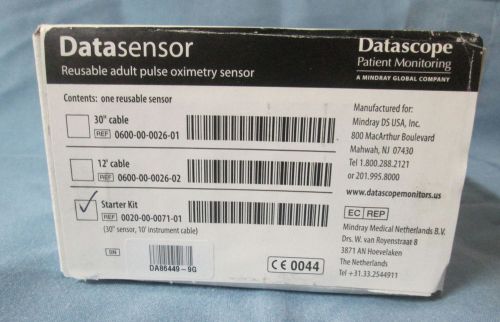

Datascope® Compatible spo2 sensor 0600-00-0026-01 boxed

Datascope® Compatible spo2 sensor 0600-00-0026-01

Datascope® Compatible spo2 sensor 0600-00-0026-01 no boxed